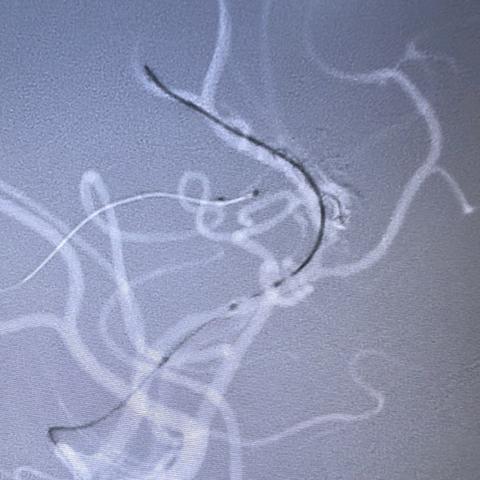

徐建国,男,45岁,额叶动静脉畸形-动静脉入路

01-26 264阅读